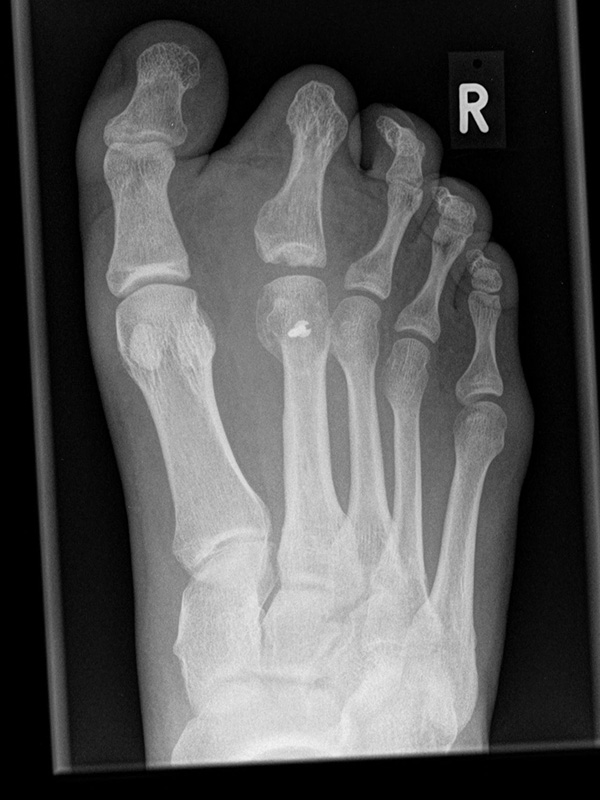

Besondere Bemerkungen zum Beispielbild:

• Schwere Hallux valgus Deformität.

• Die Sesambeine sind luxiert, ebenso das Großzehengrundgelenk. Luxation des Metatarsophalangealgelenks II.

• Degenerative Veränderungen der tarsometatarsalen (TMT) Gelenkreihe, betont TMT II und III.